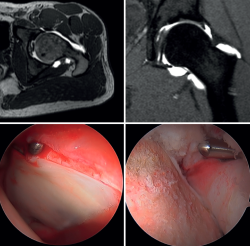

Figura 2. Choque femoroacetabular mixto en un paciente varón de mediana edad. Arriba, cortes axial y sagital de la artrorresonancia magnética preoperatoria donde se aprecia una deformidad en la transición cabeza-cuello (izquierda) y una lesión de la unión condrolabral con exceso de cobertura en la zona superior (derecha). Abajo, detalles intraoperatorios de la lesión en la unión condrolabal (izquierda) y corrección de la deformidad femoral (derecha).